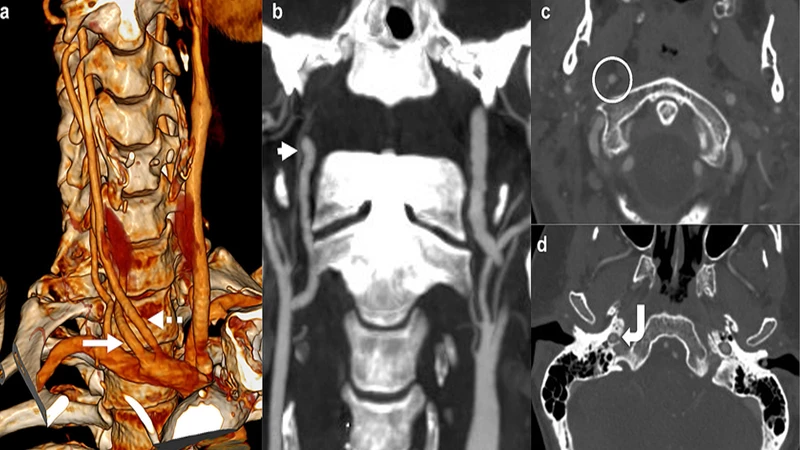

Post-Processing: Creating the 3D Images

After the raw, thin-slice images are acquired, a technologist or radiologist uses specialized software to post-process the data. This involves digitally removing structures that are not needed (like bones and organs) to isolate the blood vessels. The software can then create stunning 3D reconstructions that can be rotated and viewed from any angle.

A 3D reconstruction from a CTA of the brain's Circle of Willis, showing the intricate network of arteries.

• CTA of the Head & Neck: Used to detect aneurysms, blockages (stenosis) in the carotid arteries that can lead to stroke, and vascular malformations.